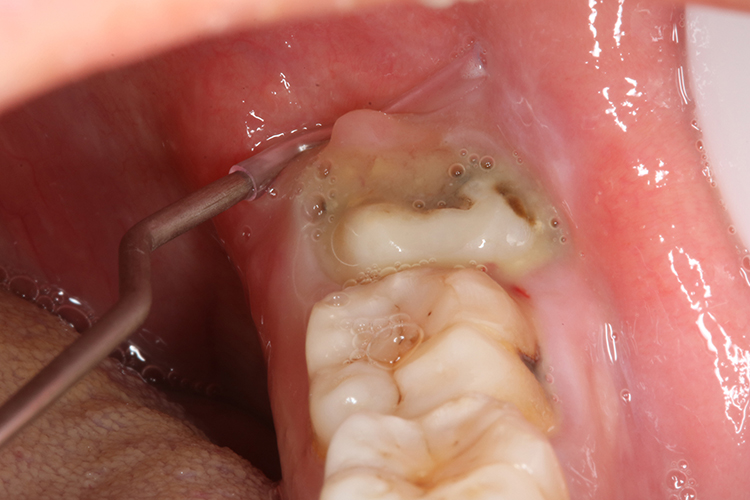

2、龋坏的程度:

- 如果龋坏已经深入牙髓,导致牙髓炎或根尖周炎,出现剧烈疼痛、牙齿松动等症状,且治疗预后不佳,拔除可能是更好的选择。

- 如果龋坏范围广泛,剩余的牙体组织过少,无法为修复治疗提供足够的支持,也难以保留。